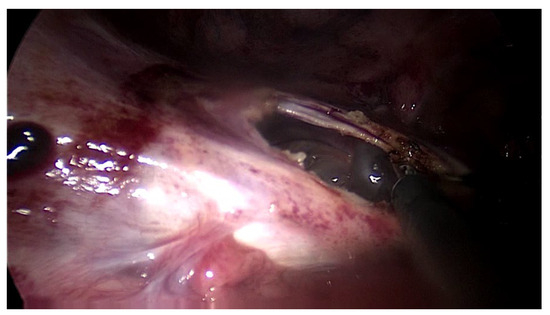

The first patient was a 25 year old woman with lupus nephritis who had undergone PD for 10 years. The PD history of the patient was associated with three episodes of peritonitis (including Mycobacterium tuberculosis, Enterococcus faecalis and Staphylococcus aureus infections, the last of which was 6 years before presentation) and negative ultrafiltration for several months requiring four hypertonic exchanges daily (2X 1.36% and 2X 3.86% Dianeal PD Solution (Baxter International)) to control overhydration. For several months, the patient was suffering from metrorrhagia and bloody effluent for several days. During hospitalization, the effluent became notably hemorrhagic with acute anemia. Emergency surgery was performed revealing hemoperitoneum due to an adnexal pathology. Intraoperatively, we found extensive peritoneal fibrosis encapsulating the small bowel loops and the organs located in the pelvis in a “cocoon” (Figure 1). Furthermore, there was significant bleeding from the site where the right adnexa should have been located and the right fallopian tube and right ovary could not be identified. A visceral “block” representing the right adnexa was dissected and isolated with great difficulty, which was resected to stop the source of the intraperitoneal hemorrhage. A final diagnosis of EPS was confirmed by the pathologist. The immediate and late postoperative outcomes were good, without any surgical complications; however, the patient subsequently died 6 months later due to a hemorrhagic stroke.

Figure 1. Intraoperative finding: thickened peritoneum.